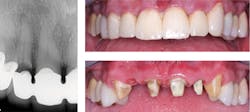

This treatment alternative has been used for nearly 60 years. The first generation had numerous challenges, and several years passed before the technique was accepted by the profession over the then-popular gold alloy full and partial crowns. The refined current generation has been used extensively with improvements and modifications since the late 1950s. Millions of restorations have been placed with a commendable service record (figures 1 and 2).

Figure 1: Failing splinted anterior restorations. Socket grafted with adequate gingival contour created. Grossly overprepared teeth due to repeated treatment.